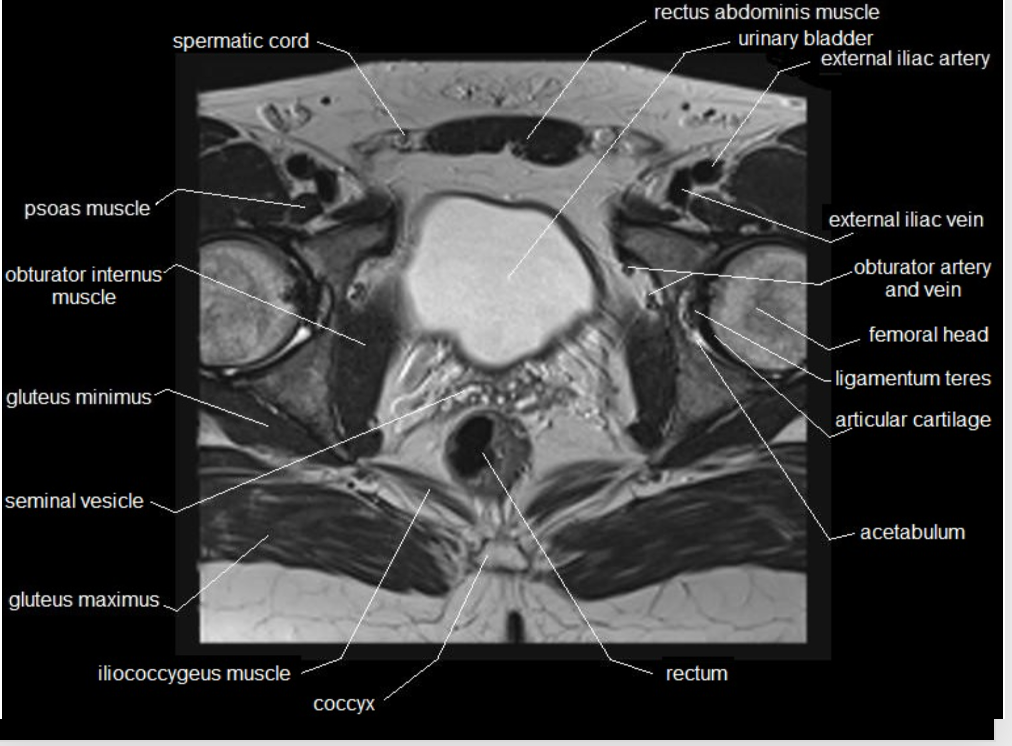

What type of imaging modality is this & fill in the blanks

MRI prostate, axial